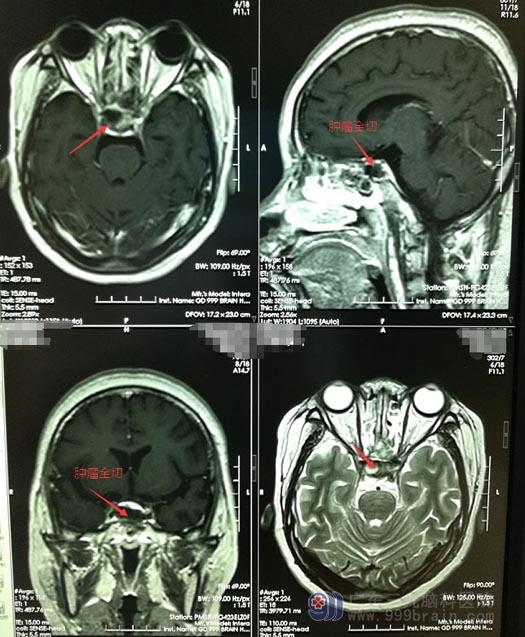

完善术前检查后,小珍在内镜下经鼻蝶鞍区行复发垂体腺瘤切除术。术中全切肿瘤,海绵窦内侧壁及颈内动脉,右侧海绵窦内侧壁无肿瘤残留,无脑脊液漏。术后病理结果提示:促肾上腺皮质激素细胞腺瘤,术后皮质醇:139.8 ug/L。出院后的小珍视力视野正常,无其他不适症状。

▲手术后